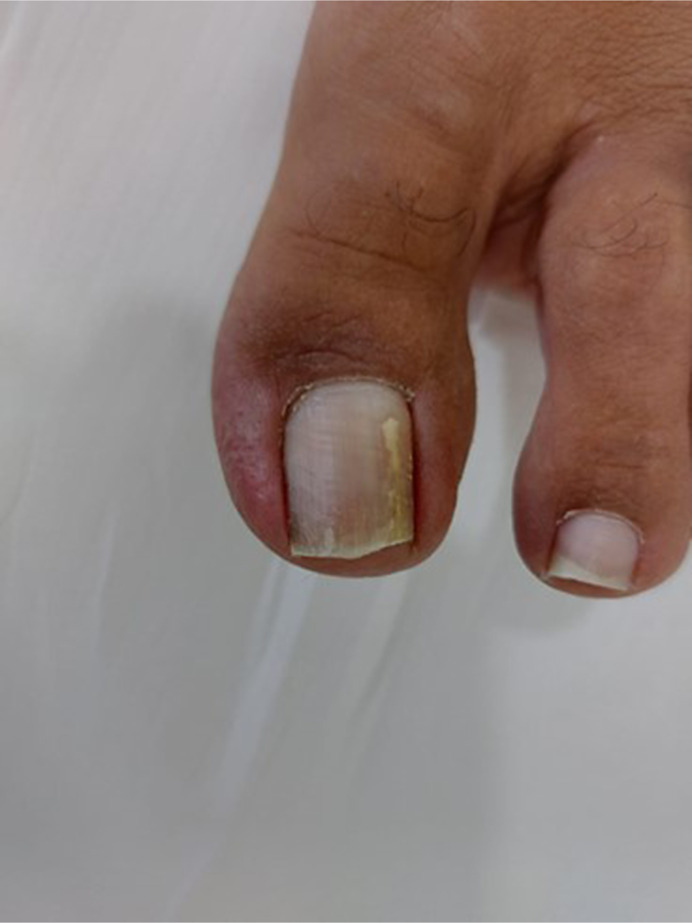

Case presentation: This case report details a 53-year-old male engineer presenting with left big toenail discoloration, revealing a C. lunata-induced onychomycosis through positive KOH preparation and culture. Given the patient's concurrent use of ticagrelor, oral terbinafine hydrochloride was chosen as a therapeutic option, taking into account potential drug-drug interactions. This approach resulted in complete resolution. The discussion emphasizes distinctions in disease severity among immunocompromised and immunocompetent patients, the potential role of trauma in Curvularia infections, and the importance of comprehensive diagnostic examinations.